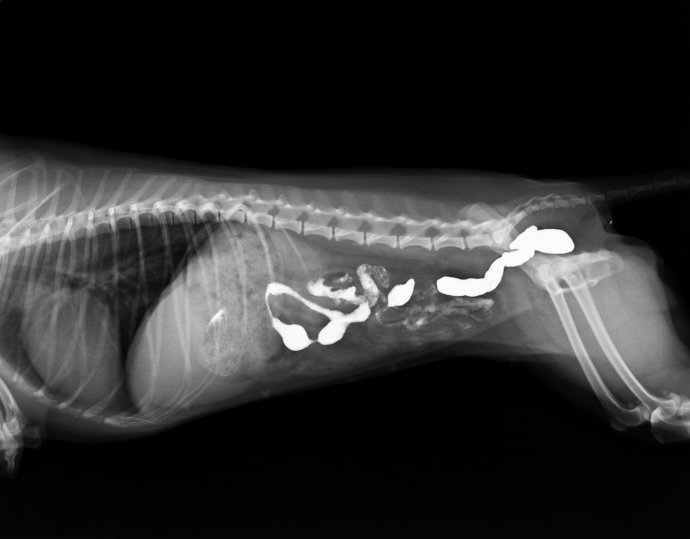

第三天,又出现呕吐,精神较差,做CR检查,发现腹部胃内有一核状异物。但体外触诊不明显,但是胃部敏感。于是手术探查。

CR结果如下:

顺着腹白线脐孔上缘手术打开腹腔,取出该犬的胃,在幽门口处触诊到一明显坚硬物体,切开胃壁,取出一杏核和少量异物。

总结,在临床中,一些密度一般的异物不是很容易看出来,所以在临床中进行影像学检查是非常有必要的,特别是对一些有胃肠反应,触诊敏感,但无法触及异物的,必要的时候我们还需要对其进行造影检查。